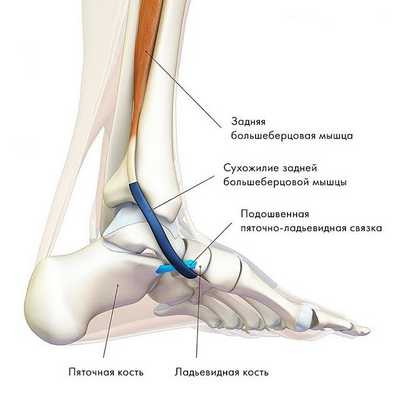

Дисфункция сухожилия задней большеберцовой мышцы

Этот синдром является причиной патологии медиальной части заднего отдела стопы, часто просмотренной и неправильно диагностированной, особенно на ранних стадиях. Это является прямым результатом потери функции сухожилия задней большеберцовой мышцы.

Хроническое воспаление ведет к дегенерации и растяжению сухожилия с формированием интерстициального отека, истончением и хроническим повреждением сухожилия. При отсутствии лечения все это ведет к нарушению выравнивания заднего и среднего отделов стопы с пронацией пятки, плантафлексии тарана, подвывиху в таранно-ладьевидном суставе и как результат формирование односторонней плоской стопы.

Задняя большеберцовая мышца активна в течение фазы опоры, включается сразу после контакта пятки с опорой и быстро прекращает сокращаться после поднятия пятки. Ее брюшко начинается глубоко внутри задней части нижней конечности, сухожилие следует вниз до задней части медиальной лодыжки, где находится кпереди от сухожилия длинного сгибателя пальцев, заднего большеберцового нейрососудистого пучка (задняя б/б артерия, вена и нерв) и сухожилия сгибателя большого пальца. Все эти структуры ограничиваются удерживателем сгибателей возле медиальной лодыжки. Сухожилие задней б/б мышцы проходит в борозде позади и ниже медиальной лодыжки, разделяясь на 3 части у медиальной стороны тарана. Передняя часть прикрепляется к бугристости ладьевидной кости, средняя часть продолжается в плантарную тарзальную область и прикрепляется к плантарной части клиновидных костей, кубовидной и в основании 2, 3 и 4 метатарзальных костей. Задняя часть внедряется как пучок в переднюю часть нижней пяточно-ладьевидной связки. Медиальная лодыжка работает как многороликовый блок, позволяя сухожилию задней б/б мышцы изменять направление тяги, и эти точки прикрепления обеспечивают супинацию заднего и среднего отделов стопы во время переноса веса, в то время как происходит стабилизация арочной конструкции среднего отдела.

Главная функция задней б/б мышцы - добиться супинации в подтаранном суставе и приведения переднего отдела стопы вокруг косой оси среднеплюсневого сустава.